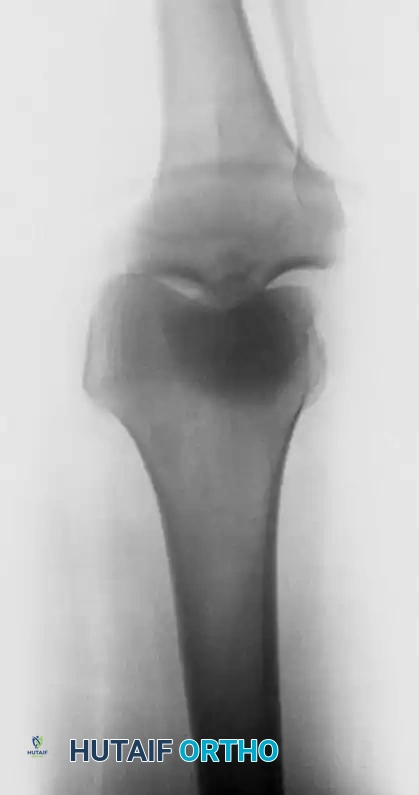

Radiographic Evaluation

Initial radiographic evaluation focuses on determining the direction of the dislocation, confirming reduction, and identifying concomitant bony injuries (e.g., Segond fractures, fibular head avulsions, or tibial plateau fractures). Anteroposterior (AP), lateral, and oblique views are mandatory.

Fig. 43-147 A: Lateral radiograph demonstrating a gross traumatic knee dislocation with posterior displacement of the tibia.

Fig. 43-147 B: Anteroposterior (AP) radiograph of the same traumatic knee dislocation.